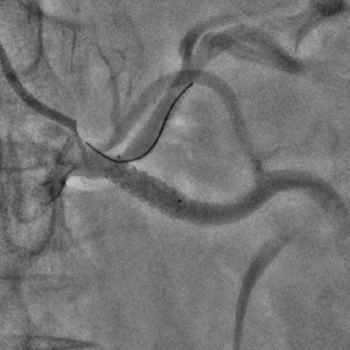

Бифуркационное стентирование почечной артерии

Ангиографическое исследование аорты и селективная ангиография сосудов почек выявило критический стеноз a. segmenti inferioris и короткую a. renalis sinistra

Операторы: Андрей Мальцев, Дмитрий Лебедев